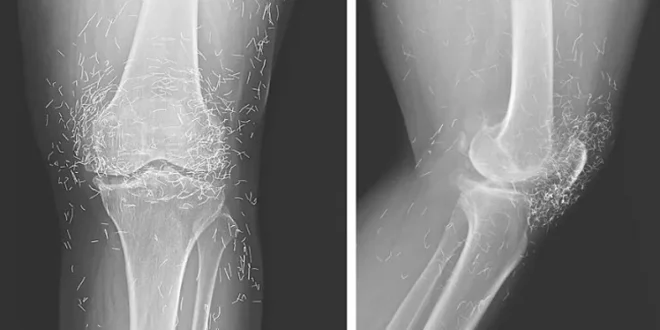

침술 금실이 무릎 관절 뒤덮어

한국 65세 여성이 양쪽 무릎 통증으로 입원했다. 엑스레이 결과 수백 개의 금실이 무릎 관절을 완전히 둘러싸고 있었다. 침술로 지속적 통증 완화를 위해 근육에 의도적으로 남긴 것이었다. 의사들은 금실 침술이 아시아에서 관절염 치료에 흔히 쓰이지만 효과 증거가 없고, 오히려 적절한 치료 시기를 놓칠 수 있다고 경고했다.